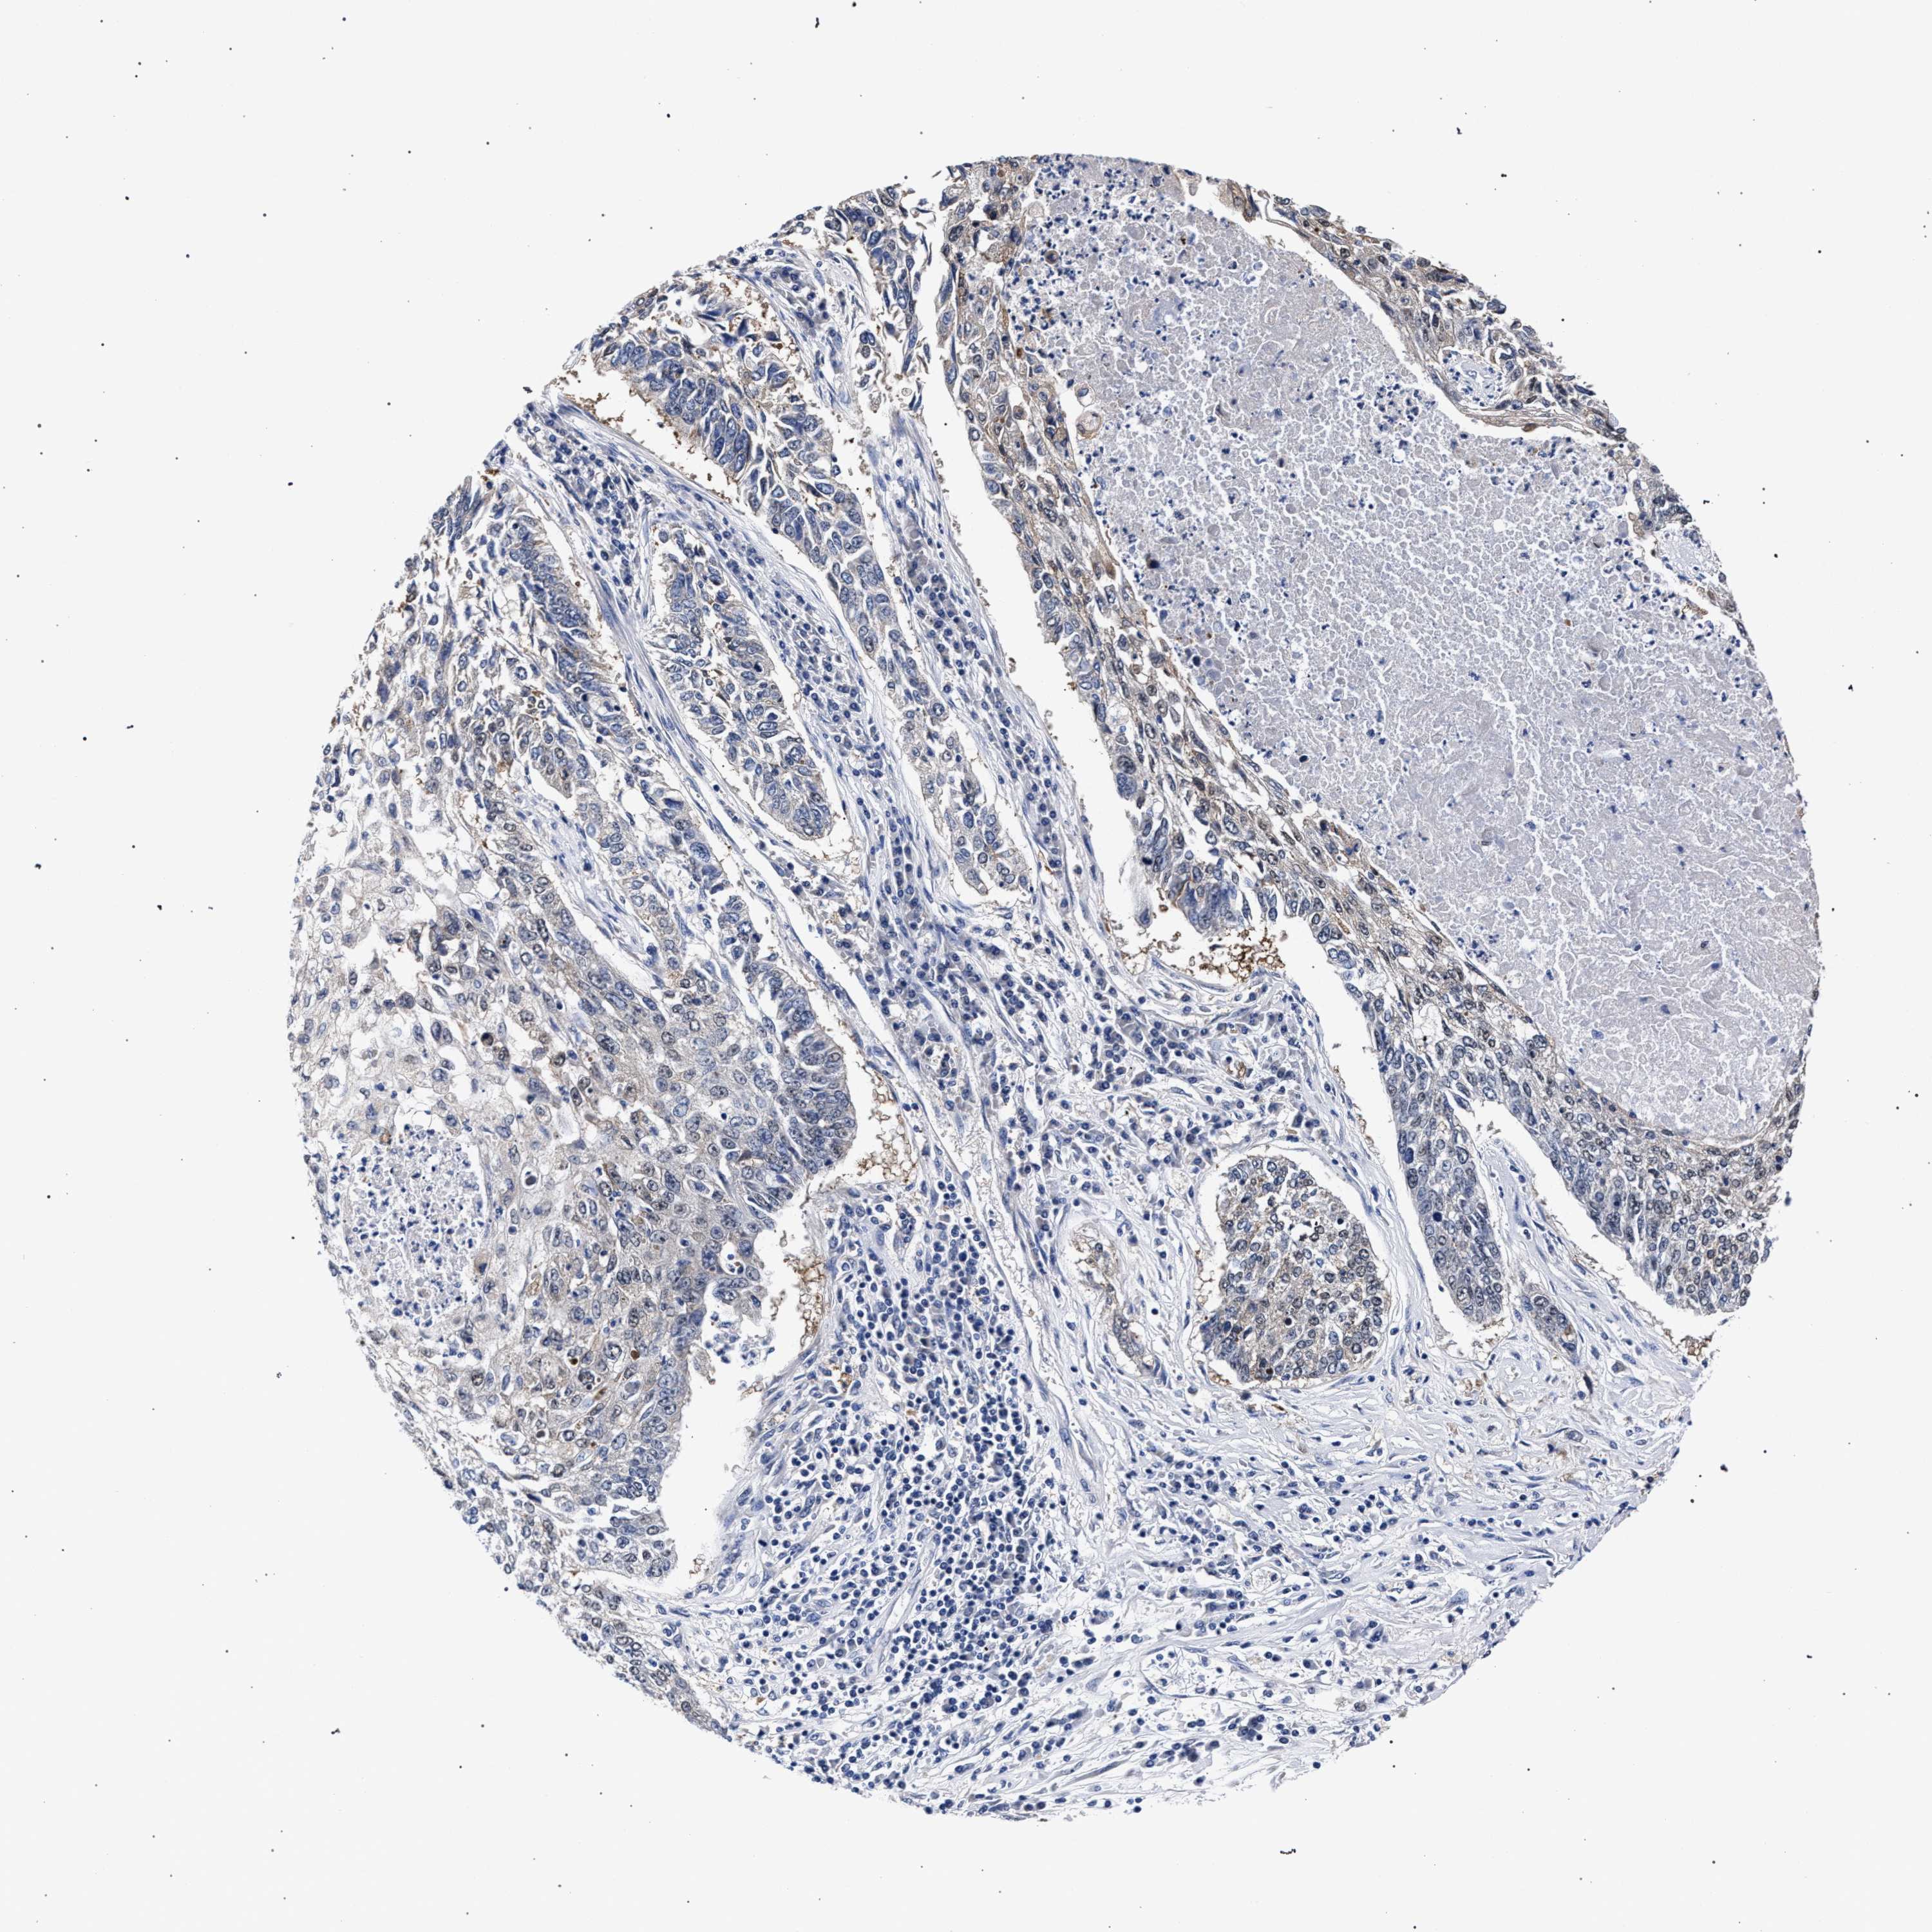

LUNG SQUAMOUS CELL CARCINOMA (TCGA) - Interactive survival scatter ploti

The Survival Scatter plot shows the clinical status (i.e. dead or alive) for all individuals in the patient cohort, based on the same data that underlies the corresponding Kaplan-Meier plots. Patients that are alive at last time for follow-up are shown in blue and patients who have died during the study are shown in red.

The x-axis shows the expression levels (FPKM) of the investigated gene in the tumor tissue at the time of diagnosis. The y-axis shows the follow-up time after diagnosis (years). Both axes are complimented with kernel density curves demonstrating the data density over the axes. The top density plot shows the expression levels (FPKM) distribution among dead (red) and alive patients (blue). The right density plot shows the data density of the survived years of dead patients with high and low expression levels respectively, stratified using the cutoff indicated by the vertical dashed line through the Survival Scatter plot. This cutoff is automatically defined based on the FPKM cutoff that minimizes the p-score. The cutoff can be changed by dragging the vertical line or by entering a cutoff value in the square labeled "Current cut-off".

Under the Survival Scatter plot the p-score landscape (black curve; left axis) is shown together with dead median separation (red curve; right axis). Dead median separation is the difference in median mRNA expression between patients who have died with high and low expression, respectively. It is calculated as follows: median FPKM expression of dead patients with high expression - median FPKM expression of dead patients with low expression. This is intended to aid the user in visually exploring custom cutoffs and the associated p-scores and dead median separation.

Individual patient data is displayed and can be filtered by clicking on one or more of the category buttons on the top of the page. Categories describing expression level and patient information include: high, low, alive, dead, female, male and tumor stages. The scale of the x-axis can be toggled between linear and log-scale by clicking on the "x log" button. Mouse-over function shows TCGA ID, patient information and mRNA expression (FPKM) for each patient.

& Survival analysisi

Kaplan-Meier plots summarize results from analysis of correlation between mRNA expression level and patient survival. Patients were divided based on level of expression into one of the two groups "low" (under cut off) or "high" (over cut off). X-axis shows time for survival (years) and y-axis shows the probability of survival, where 1.0 corresponds to 100 percent.

RBM33 is not prognostic in Lung Squamous Cell Carcinoma (TCGA)

: 13.26